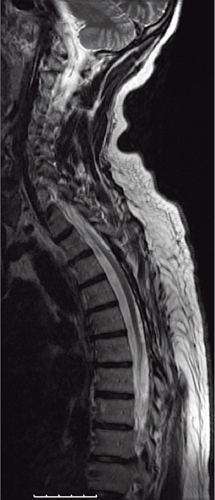

På akutmottagningen tolkades patientens besvär som neuropati, och han behandlades med injektion tiamin (Betabion). Eftersom patienten försämrades ytterligare, genomfördes samma dag akut MRT av hela ryggen, vilken visade ett uttalat ryggmärgsödem från bröstrygg till conus medullaris. Dorsalt om ryggmärgen sågs vidgade blodkärl, varför man misstänkte att det rörde sig om en spinal dural arteriovenös fistel (Figur 1). Neurokirurgisk klinik kontaktades för övertagning.

Diagnostik. Den kliniska bilden och spinal MRT är helt avgörande för diagnosen. Okunnighet hos kliniker eller radiolog kan få som konsekvens att diagnosen ställs för sent eller inte alls, medan patienten utvecklar en obotlig parapares. De typiska fynden vid MRT är ödem och lätt svullnad av ryggmärgen torakolumbalt samt vidgade blodkärl (vener) dorsalt perimedullärt. Ödemet uppvisar hög signal centralt i ryggmärgen på T2-viktade bilder. De vida perimedullära venerna syns i cerebrospinalvätskan som slingriga strukturer med låg signal på T2-viktade bilder och hög signal på T1-viktade bilder efter intravenös kontrastmedelstillförsel.